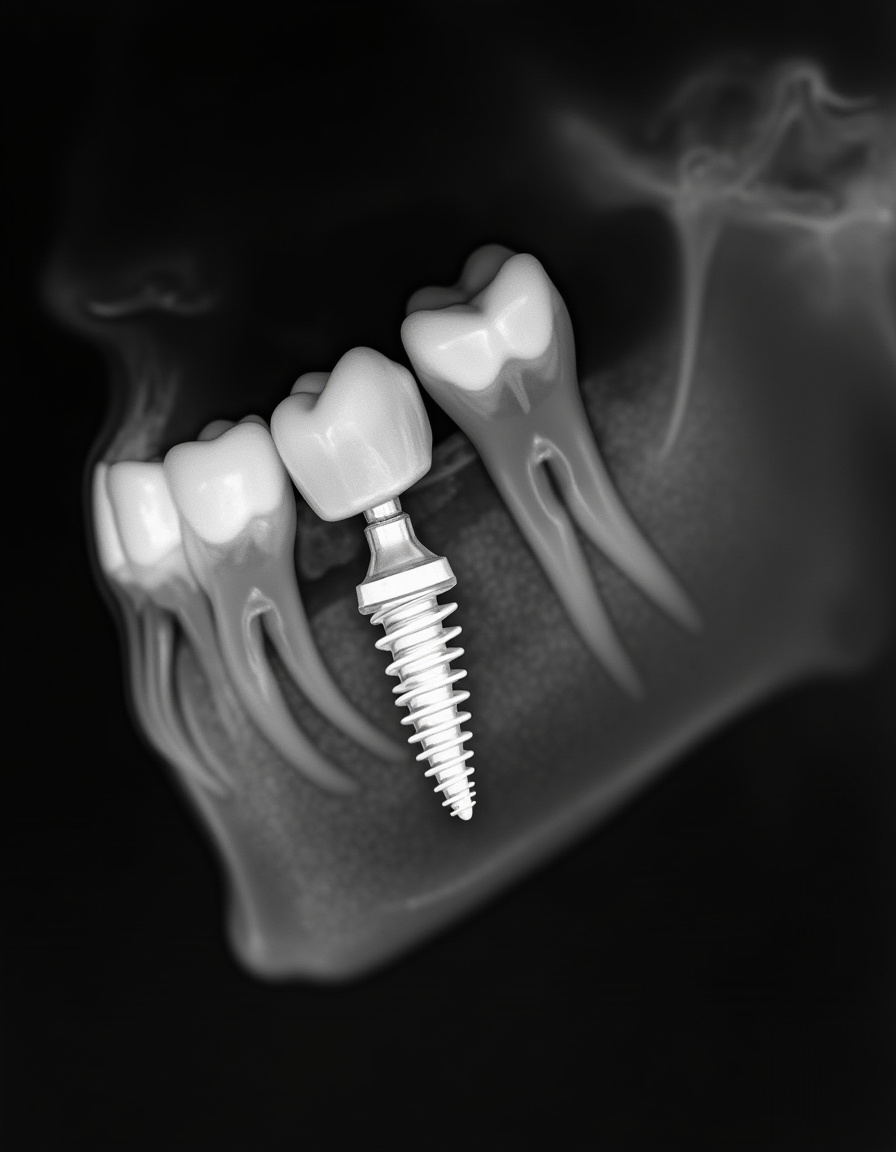

While that titanium post should last forever, the crown (the part that looks like a tooth) will wear down eventually. Most patients need a new one every 10-15 years, costing around $1,000-$2,000.

So over 30 years, you might replace it 2-3 times, totaling $3,000-$6,000. Sounds like a lot until you compare it with replacing entire bridges or dentures multiple times over those same decades.

The Connector Piece

The abutment (the connector between the implant and crown) rarely causes trouble, but occasionally needs replacement at $300-$500. Maybe once or twice in your lifetime, adding roughly $500-$1,000 to your lifetime tally.